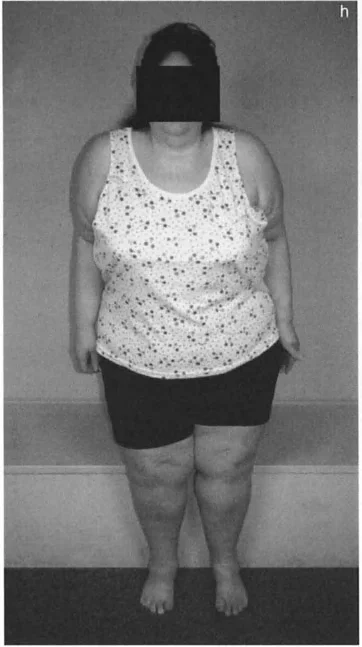

أعراض تشوهات العظام وكيف تؤثر على حياتك

تتنوع أعراض تشوهات العظام بشكل كبير اعتمادًا على نوع التشوه وموقعه وشدته. يمكن أن تؤثر هذه الأعراض بشكل كبير على جودة حياة المريض، من الأنشطة اليومية البسيطة إلى المشاركة في الأنشطة الرياضية.

تغير في شكل الطرف:

- يُلاحظ انحناء واضح في الساق أو الفخذ، أو دوران غير طبيعي في القدم أو الطرف.

- قد يبدو أحد الطرفين أقصر أو أطول من الآخر، مما يؤثر على تناسق الجسم.

تأثيرات نفسية واجتماعية:

- يمكن أن تؤثر التشوهات المرئية أو الصعوبات الحركية على ثقة المريض بنفسه، وتؤدي إلى العزلة الاجتماعية أو الاكتئاب.

- قد يجد الأطفال والمراهقون صعوبة في الاندماج مع أقرانهم في الأنشطة البدنية.